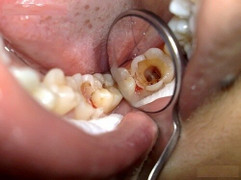

Mọc răng khôn được coi là nỗi sợ của mỗi người vì cảm giác khó chịu mà nó đem lại.

Điều đáng sợ nhất của việc nhổ răng khôn là cảm giác đau, khó chịu của những ngày sau đó, nhưng việc chăm sóc vết thương tốt sẽ đẩy nhanh sự hồi phục.

Các chuyên gia cho biết, răng khôn khi mọc lệch có thể gây nhiều biến chứng nguy hiểm tới tính mạng.

Răng khôn thường mọc lệch, chèn ép các răng khác và gây cảm giác đau nhức cho chúng ta dấn đến đau đầu, lợi hoặc nhiễm trùng miệng.